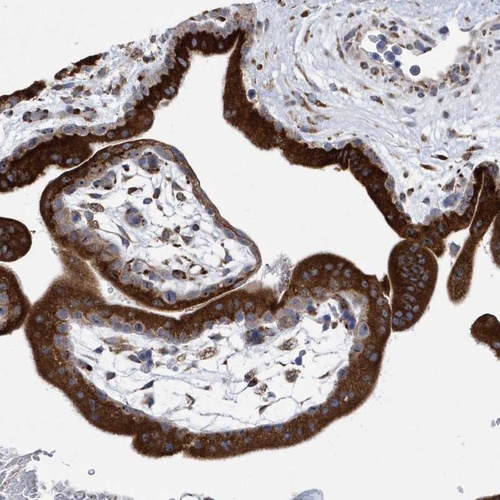

Immunohistochemical staining of human placenta shows strong cytoplasmic positivity in trophoblastic cells.